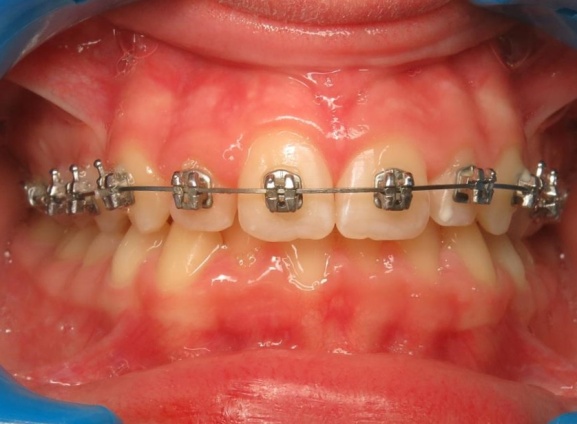

3 - Phase 2 : traitement orthodontique- alignement des dents et occlusion

Le traitement a d’abord consisté à corriger le décalage entre les bases osseuses des mâchoires par une phase orthopédique. Une fois cet équilibre rétabli, un appareil multiattaches a été mis en place pour aligner les dents sur des bases désormais bien positionnées. La dernière étape a permis de peaufiner les contacts entre les dents afin d’obtenir une occlusion fonctionnelle et stable.